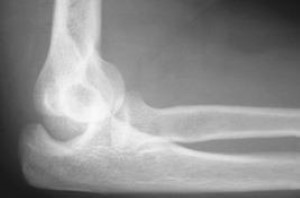

Imaging Tests

An X-ray is necessary to determine if there is a bone injury. X-rays can also help show the direction of the dislocation.

• X-rays are the best way to confirm that the elbow is dislocated.

• If bone detail is difficult to identify on an X-ray, the doctor may order a computed tomography (CT) scan.

• If it is important to evaluate the ligaments, a magnetic resonance imaging (MRI) scan can be helpful; however, an MRI is rarely required at the time of the dislocation.

After the X-ray confirms the dislocation, the doctor will set (reduce) the elbow. If a CT scan and/or MRI scan is needed, they are usually done after the dislocated elbow has been put back in place.

After elbow reduction

Normal alignment after the elbow has been reduced.

After the elbow has been restored to the correct position (reduced), a splint is applied to keep the elbow still. This protects the elbow to avoid further injury. The splint should not be removed until you follow up with a physician.